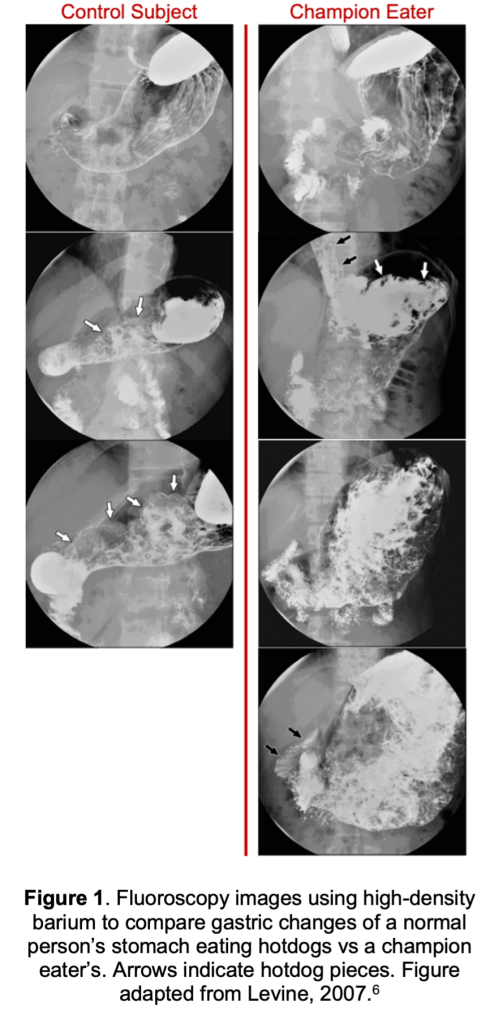

The stomach was one of the first organs to be studied with scientific stomach observations dating back to the 1500s1. The volume of the average empty human stomach is 45-75 mL, yet the stomach can expand during feeding to anywhere from 1.5 liters in lean adults, to 4 liters in those with binge eating disorders2–4. To visualize this, think of a flattened balloon sitting in your abdomen, then consider how big that balloon is when fully blown up! Your stomach can stretch to over five times its size because it is a smooth muscle tube5. Consider Joey Chestnut, who holds over 46 food eating records, including his record of eating 74 Nathan’s Famous hot dogs in 10 minutes. Figure 1 shows how much the human stomach can distend for competitive eaters who practice this stretching6.